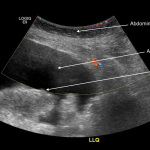

ABDOMINAL COLOR DOPPLER ULTRASOUND

Key features of ascites seen in this imaging modality are:

- Anechoic nature: ascites will allow sound waves to pass through it, so it will appear black/dark on ultrasound.

- Absence of color doppler signal: there should be no flow signal seen throughout the ascites. Ascites should not move around if the patient is still, and it should not contain vessels.

The gallery below organizes examples of how ascites will appear on abdominal color doppler ultrasound. Click on the thumbnails below to open up the gallery: